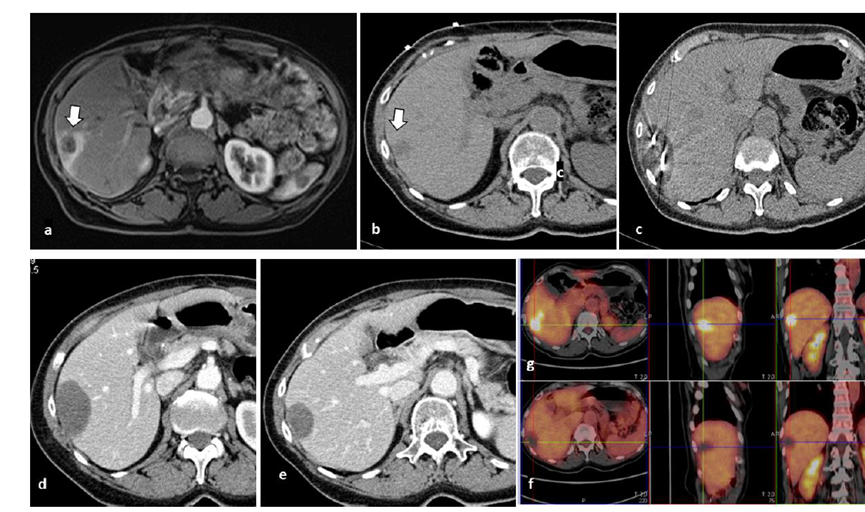

CT引導(dǎo)的冷凍消融

undefined

冷凍消融膽囊附近腫瘤病灶

(A)動(dòng)脈期 MRI 顯示膽囊附近有外周增強(qiáng)病變(箭頭)。

(B)手術(shù)過程中 CT 顯示冷凍探針位于病灶內(nèi)。

(C)消融后,術(shù)后 1 個(gè)月CT 顯示完全消融(箭頭)。

冷凍消融肝包膜下肝細(xì)胞癌

(A)動(dòng)脈期CT圖像顯示有一個(gè)包膜下結(jié)節(jié)(箭頭)。

(B)門靜脈期CT圖像顯示病灶區(qū)(箭頭)。

(C) 在手術(shù)過程中的CT顯示一個(gè)冷凍探針位于病灶內(nèi)。

(D)消融后,術(shù)后1個(gè)月影像CT顯示完全消融。